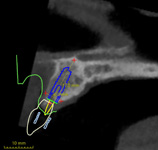

Chirurgicko-protetický plán vychází z 3D rentgenu čelisti, otisku zubů a dásně (scanu zubů a dásně) a finálního návrhu protetické náhrady. Na základě těchto dat je v plánovacím softwaru coDiagnostiX vytvořena chirurgická šablona,

která je následně vytištěna na 3D tiskárně a použitá v den výkonu. Od roku 2014 jsme tuto metodu jako první v ČR začali využívat a nadále se podílíme na vývoji a vylepšování chirurgických šablon pro ještě přesnější a předvídatelnější výsledky.

Jedná se o externí plánovací program, spojený se zubní laboratoří a frézovacím centrem, který využívá dat získaných z 3D rentgenu čelisti, otisku zubů a dásně (scanu zubů a dásně) a finálního návrhu protetické náhrady.

Tento program umožňuje tříprostorovou počítačovou simulaci při plánování pozic implantátů. Součástí programu je i databáze, ve které mohou být uloženy všechny typy implantátů od všech výrobců, včetně jejich délek, průměrů i tvarů.

Lékař si vytvoří všechny typy zobrazení potřebných pro naplánování – tedy 2D snímky (panoramatický), příčné řezy i 3D model.

Vidí zde i důležité anatomické útvary – čelistní dutinu, průběh nervu atd. Po proměření množství kosti – šířky i výšky vybere z databáze vhodný typ implantátu a umístí ho do požadované lokality. Ihned vidí jeho pozici ve všech 3 rovinách

a na všech snímcích i 3D modelu. Může upravovat podle potřeby jeho pozici, sklon atd.

Všechny vybrané a správně umístěné simulované implantáty se ukládají do „počítačové karty“ pacienta s jejich pozicí, délkou, průměrem, typem i sklonem. V programu také lékař navrhuje chirurgické šablony pro řízenou nebo navigovanou implantaci.

Lékař i pacient tedy ještě před vlastní operací vidí, jak by mělo ošetření probíhat a vypadat.